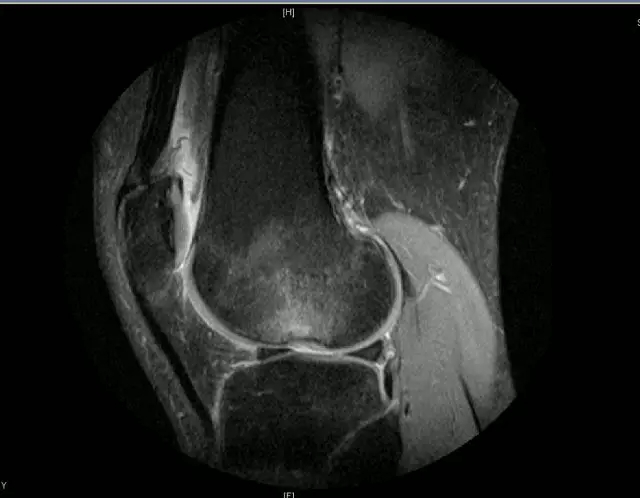

正常的膝关节

韧带结构:形态,张力,质地,连续性

半月板:完整性,形态,质地